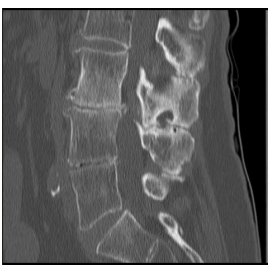

O corte tomográfico sagital da coluna lombar abaixo ilustra claramente alterações que possibilitam alguns diagnósticos, dentre os quais podemos citar:

Doença de Baastrup.

Doença de Scheuermann.

Hiperostose esquelética idiopática difusa (DISH).

Espondilite anquilosante.